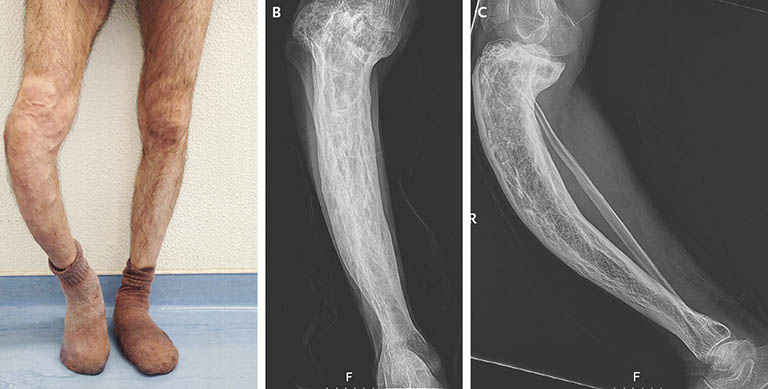

- Biến dạng xương: Bệnh Paget xương có thể gây ra biến dạng xương, làm cho xương trở nên cong hoặc dễ gãy hơn. Biến dạng xương cũng có thể gây ra các triệu chứng khác như khó thở và đau lưng.

- Kích thước xương tăng: Bệnh Paget xương có thể làm cho xương trở nên dày hơn và kích thước tăng lên. Điều này có thể gây ra các triệu chứng như khó thở và đau lưng.

- X-quang: để xác định mức độ bệnh và vị trí của các vùng xương bị ảnh hưởng.